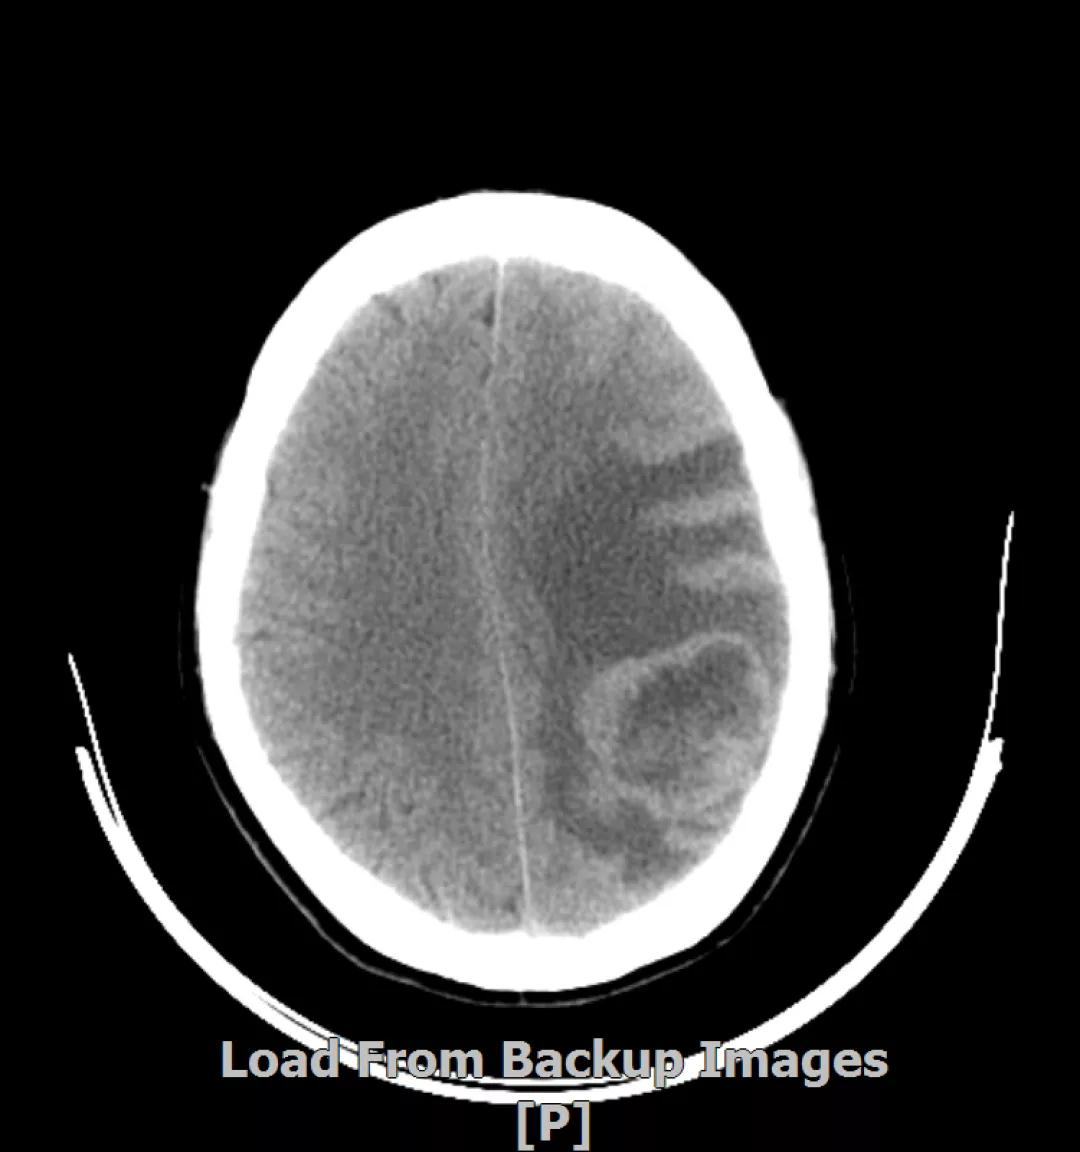

5. 病情第4次进展:2019年11月患者出现视野模糊等症状

头颅增强MR:左侧顶颞叶见片状T1WI低信号、T2WI高信号影,病灶大部信号接近脑脊液,增强后术区边缘左侧顶叶见结节状强化影,大小约10x8x11mm,较2019-03- 15MR老片大致相仿;右侧脑室三角区见结节样T1WI等低信号、T2WI不均匀稍高信号影,增强后不均匀明显强化,大小约24x18x20mm,较2019-03-15MR老片明显增大;两侧半卵圆区、侧脑室旁见较对称片状T1WI低信号、T2WI高信号影,增强后未见明显强化,较前片相仿;余脑室、脑池、脑沟大小形态可,中线结构向左偏移。

左顶颞叶转移瘤治疗后改变

右侧脑室三角区旁强化结节,较2019-03-15MR老片明显增大 左侧顶叶强化结节,较2019-03-15MR老片大致相仿

两侧脑室旁云絮状异常信号,考虑放疗后改变